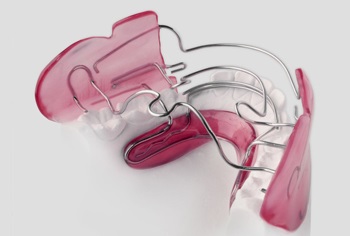

Fotografii cu exemple de dispozitive ortodontice

Alegerea unui dispozitiv ortodontic depinde de complexitatea corecției efectuate, de dorințele clientului clinicii, precum și de alte criterii, cum ar fi costul și durata tratamentului.

Toate dispozitivele pe care ortodontul le utilizează în lucrarea sa sunt detașabile și nu pot fi îndepărtate. Printre acestea se numără și cele pe care se poate purta un anumit număr de ore pe zi. Acestea sunt folosite de copiii cu mușcături mixte și cu lapte. Dispozitivele ortodontice se găsesc:

Aparatul dvuhsheljustnye afectează dezvoltarea și creșterea maxilarului, poate dezactiva de obiceiurile proaste care au un efect negativ asupra formării mușcăturii. La baza lor, acestea sunt protezele dentare obișnuite, având un aspect diferit.